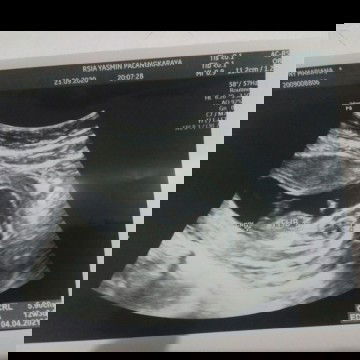

Hai bunda bunda... Aku mau curhat nih, apakah selama hamil tidak diperbolehkan makan sambal?? Oh ya, foto USG ini diambil bulan lalu saat aku hamil 12 minggu 3 hari. Dan sekarang sudah 14 minggu 2 hari. Dokter menyarankan untuk sementara waktu berhenti dulu mengosumsi makanan pedas, asem dan kafein. Tapi ada satu makanan yang sulit sekali aku lepaskan, dan aku sudah puasa sejak periksa USG yaitu makanan pedas. Aku mau nih, apakah aku tidak boleh makan makanan pedas sampai lahiran nanti? Terima kasih.